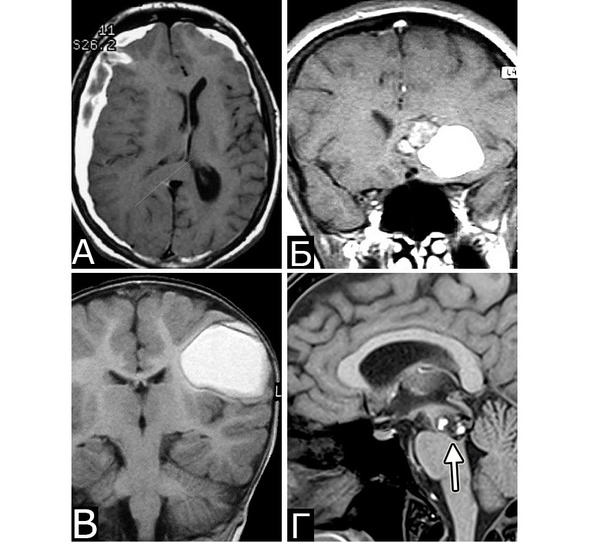

Кровоизлияния из каверном могут быть как достаточно объемными, так и протекать в виде микрогеморрагий. Морфологические исследования и данные МРТ показали, что следует различать кровоизлияния, происходящие «внутри» мальформации, и кровоизлияния, выходящие за границы каверномы. В случаях с кровоизлияниями с образованием объемных гематом вокруг последних со временем может формироваться капсула. После рассасывания гематомы клинические симптомы в значительной степени регрессируют. Варианты кровоизлияний можно достаточно точно диагностировать по данным МРТ (рис. 33).

Рис. 33. Варианты кровоизлияний из кавернозных мальформаций. А – КМ поверхностных отделов правой лобной доли. Массивное субарахноидальное кровоизлияние с формированием субдуральной гематомы справа. Б – КМ медиальных отделов левой лобной доли. Кровоизлияние с формированием большой гематомы вне границ каверномы. В – кровоизлияние из КМ в виде крупной однокамерной инкапсулированной гематомы. Г – небольшие кровоизлияния в строме КМ среднего мозга. Все КМ подтверждены гистологически